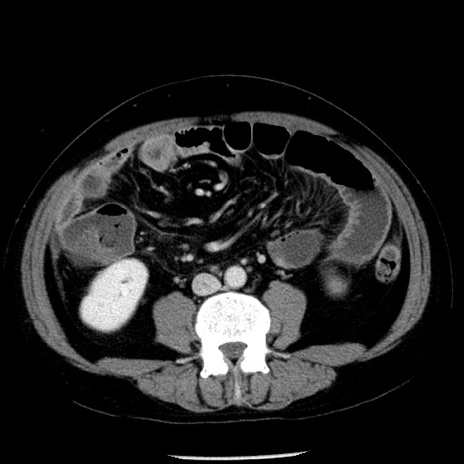

冠状断像

【症例】40歳代男性

【現病歴】2日前から胃痛あり。徐々に周期的な激痛に変化した。本日になっても激痛があるため受診。

【身体所見】意識清明、BT 38-39℃台あり、腹部:膨満、やや硬、右下腹部に圧痛あり。

【データ】WBC 8500、CRP 23.26